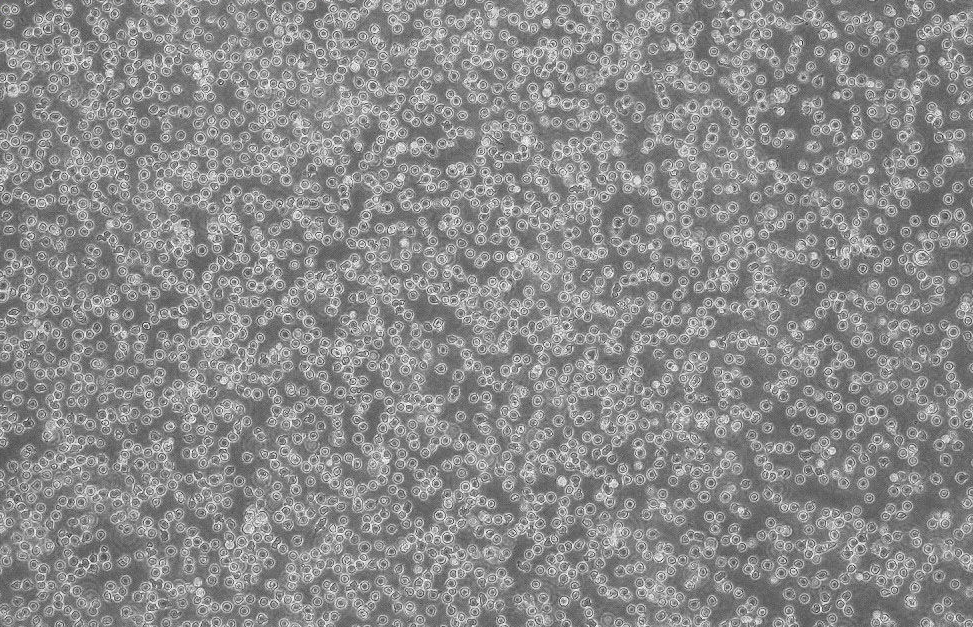

形态 |

淋巴细胞样 |

生长特征 |

悬浮生长 |